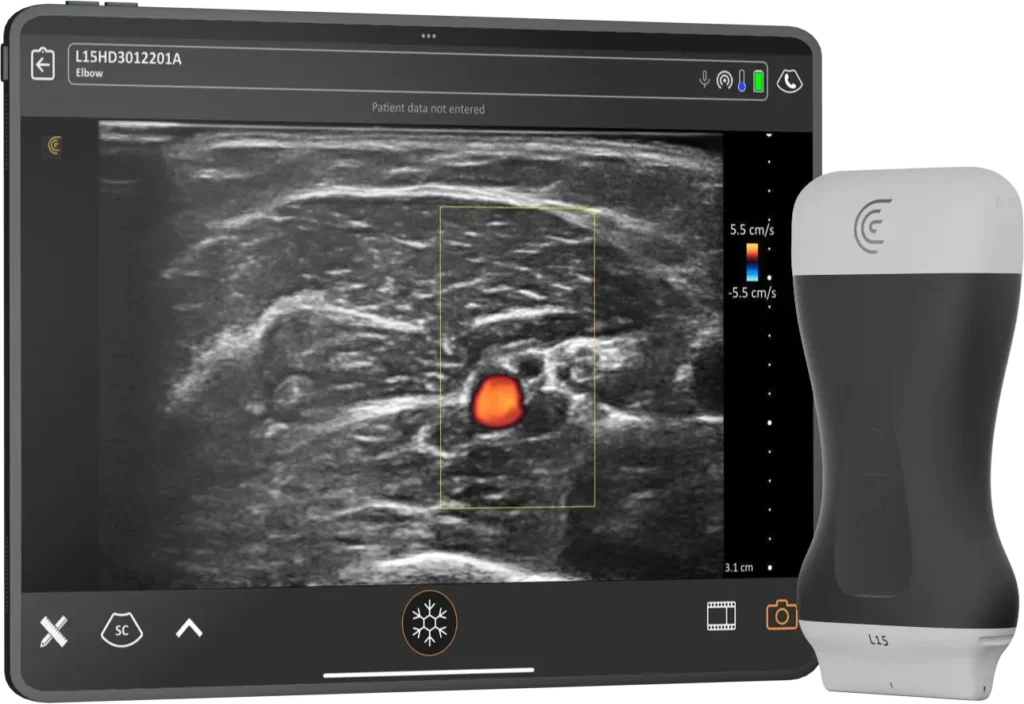

Clarius Intelligence combines smart tools and automation to streamline scanning and keep you focused on your patient.

Your phone and Clarius are all you need to take the power of ultrasound with you wherever you go.